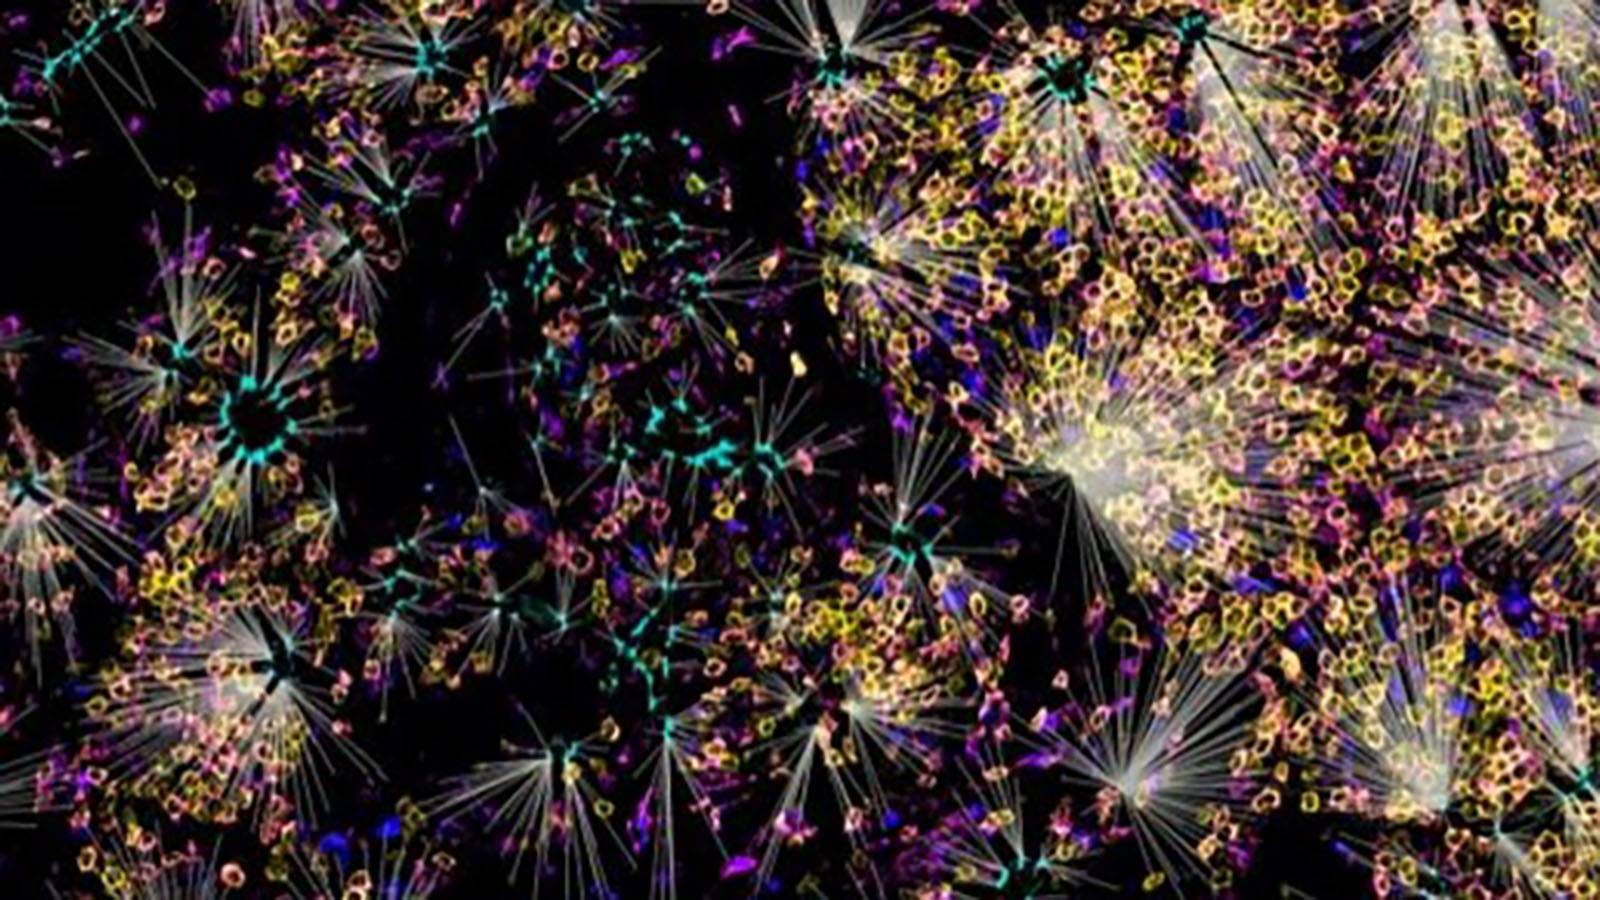

CODEX of intestine from Dr. John Hickey at Stanford